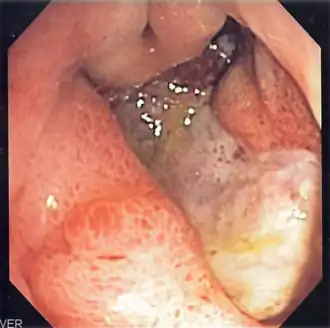

![]() Изображение язвы желудка, полученное с помощью эндоскопа | |

Наиболее информативным в диагностике язвенной болезни желудка и 12-перстной кишки является эндоскопическое исследование, которое визуально подтверждает наличие язвенного дефекта, позволяет уточнить его локализацию, глубину, форму, размеры, позволяет оценить состояние дна и краев язвы, выявить сопутствующие изменения слизистой оболочки. При проведении эндоскопического исследования имеется возможность произвести прицельную биопсию — «отщипывание» кусочка ткани из краев или дна язвенного дефекта посредством специального инструментария. Полученный таким образом биоптат (кусочек ткани) направляется на гистологическое исследование, которое позволяет выявить возможную раковую природу обнаруженного язвенного дефекта (язвенная форма рака желудка).